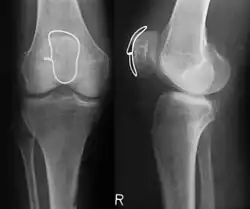

Das Verfahren wird chirurgisch nur bei Brüchen eingesetzt, die in Gelenken verlaufen und deren Bruchstücke unter Zugspannung von Sehnen stehen, so dass der Muskelzug die Bruchstücke zwangsläufig voneinander entfernt. Solche Brüche entstehen daher auch bei Stürzen immer durch eine Kombination aus direkter Krafteinwirkung auf den Knochen und durch die einwirkende Zugspannung der Muskulatur. Typische Beispiele für solche Brüche sind die Querfrakturen des Ellenhakens und der Kniescheibe durch Sturz oder Anprall auf den Ellenbogen und aufs Knie mit entsprechender Muskelanspannung zur Abwehr des Sturzes. Man könnte sehr eingeschränkt auch die Abrisse am Innen- und Außenknöchel des oberen Sprunggelenkes und an der Basis des 5. Mittelfußknochens sowie am Tuberkulum majus des Oberarmknochens zu diesen Abrissfrakturen zählen und sie auch mit einer Drahtschlinge behandeln. Eine echte Zuggurtungswirkung entsteht dabei nicht.

Das Prinzip des Verfahrens besteht darin, dass die auf die Fragmente einwirkenden Zugspannungen von einer Drahtschlinge aufgefangen werden, die um die Sehnenansätze oder am Knochen angebracht wird und möglichst gelenkfern auf den Fragmenten aufliegt. Bei der aktiven Bewegung (Beugung) des Gelenkes nach der Operation führt die einwirkende Zugspannung innerhalb des Gelenkes (also gegenüber der Drahtschlinge) zu einer Druckspannung, die den Bruchspalt zusammenschiebt. Damit werden die Bruchstücke in korrekter Position gehalten und der Bruch kann sicher ausheilen. Dieses einfache Grundprinzip (Umwandlung von Zug- in Druckspannung) ist mit einem Minimum an Materialkosten (wenige Cent für den Edelstahldraht) und mit einem relativ kleinen operativen Eingriff umzusetzen, was den Siegeszug dieses Verfahrens seit seiner ersten Beschreibung 1958 erklärt. Alle einfachen Rissbrüche der Kniescheibe und des Ellenhakens werden fast ausschließlich mit diesem Verfahren operiert. Und einen weiteren Vorteil hat das Verfahren: Die Nachbehandlung erfolgt ausschließlich funktionell, d. h., korrekterweise darf keine Gipsanwendung oder Ähnliches durchgeführt werden, es handelt sich also um ein klassisches dynamisches Verfahren. Um das Verfahren auch bei komplizierteren Brüchen mit mehreren Bruchstücken durchführen zu können und um auch in Streckhaltung die Bruchstücke nicht unter der Zugspannung klaffen zu lassen, hat sich die Verwendung von etwa zwei zusätzlichen geraden Drähten bewährt, die unter Einrichtung der Bruchstücke längs von dem einen Bruchstück über den Bruchspalt in das andere Bruchstück gebohrt werden. Wo die Drähte aus dem Knochen im Ansatzbereich der Sehnen aus dem Knochen ragen, wird die Zuggurtungs-Drahtschlinge statt nur um den Sehnenansatz um ebendiese Drahtenden gelegt und damit eine weitere Erhöhung der Stabilität erreicht.

-

Klassische Zuggurtung einer Patellafraktur -

Erweiterte Zuggurtung einer Patellafraktur (mit K-Drähten) -